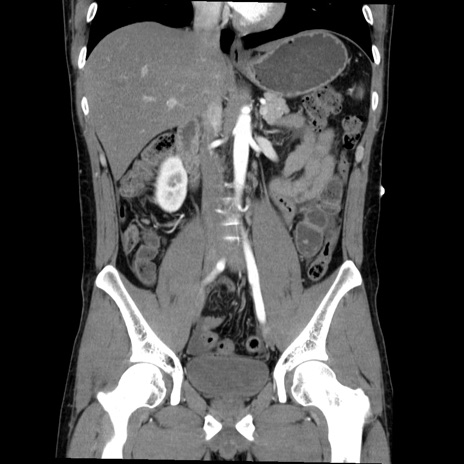

症例36(冠状断像)

【症例】20歳代 男性

【主訴】心窩部痛

【現病歴】今朝より上腹部痛あり。一旦軽快していたが再度出現したため救急要請。昨日夕に白身の魚を含む刺身を食べた。

【身体所見】BP 136/89mmHg、HR 74/min、BT 37.0℃、腹部:膨満、軟、心窩部に圧痛あり。反跳痛なし、筋性防御なし、腸雑音やや亢進あり。

【データ】WBC 17700、CRP 0.48

横断像